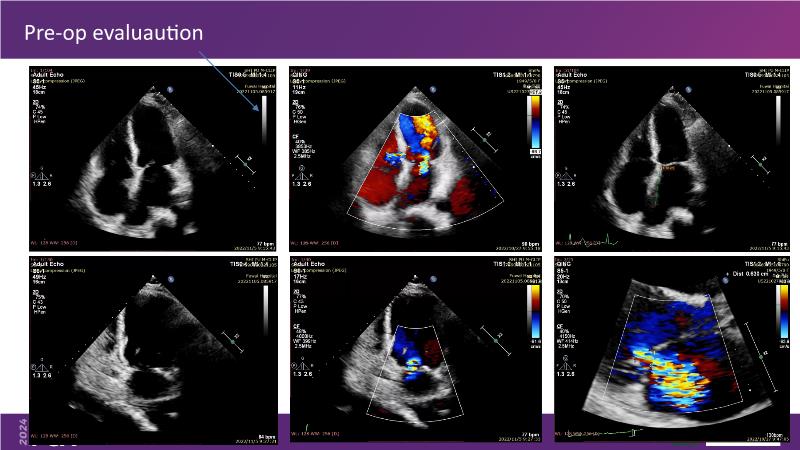

Watch this session to gain insights into the clinical evidence of mitral TEER therapy for the Asian population, learn techniques for implanting a MitraClip in patients with challenging anatomy, and understand how to use the four clip sizes for optimal outcomes. The session also covers educational aspects of clipping in dextrocardia, the benefits of reserve bending of the transseptal needle for tenting and puncture, new steering maneuvers for dextrocardia patients, and the importance of understanding anatomy and collaborating closely with the echo team for success.